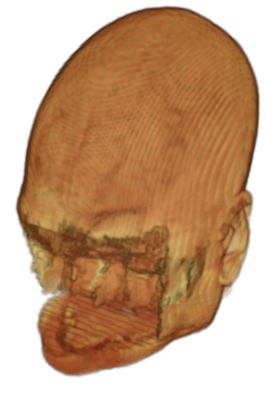

The digitalization of heath records has increased the risk of –and impact of– large scale data leaks. Although data compliance standards have been enacted to protect health records (HIPAA and GDPR), privacy of medical data is a growing concern. Three-dimensional scans such as magnetic resonance images (MRI) and computed tomography (CT), for example, contain an intrinsic privacy risk [Lotan et al.(2020)Lotan, Tschider, Sodickson, Caplan, Bruno, Zhang, and Lui]. Detailed renderings of the head can be crafted from 3D scans using techniques such as volumetric raycasting, as in Figure 1. This vulnerability can expose the patient’s identity if the renderings are matched to a face database [Mazura et al.(2012)Mazura, Juluru, Chen, Morgan, John, and Siegel, Lotan et al.(2020)Lotan, Tschider, Sodickson, Caplan, Bruno, Zhang, and Lui].

To prevent these types of attack, medical scans are currently de-identified using crude removal-based techniques [Bischoff-Grethe et al.(2007)Bischoff-Grethe, Ozyurt, Busa, Quinn, Fennema-Notestine, Clark, Morris, Bondi, Jernigan, Dale, Brown, and Fischl, Schimke et al.(2011)Schimke, Kuehler, and Hale, Milchenko and Marcus(2013)] which seek to remove privacy-sensitive parts of the head (examples in Figure 3). However, as we demonstrate, these existing techniques fail to reliably hide the patient’s identity – or they are so aggressive that they impair further medical analyses. A better solution is needed.

![]() |

Therefore, in this work, we define a new class of de-identification techniques that remodels the privacy-sensitive regions without altering the content of medically relevant data (see Figure 1). Under such a remodeling approach, the face, eyes, oral and nasal cavities, etc. should exhibit realistic appearance and structure of appropriate size, but should otherwise be independent of the original data. To solve this task, we propose a novel model called Convex Privacy GAN, or CP-GAN, that conditions on a convex hull of the skull extracted from the scan to be de-identified. The generator learns to synthesize volumes that preserve medically-sensitive regions such as the brain, while non-invertibly remodeling privacy-sensitive characteristics from the original scan.